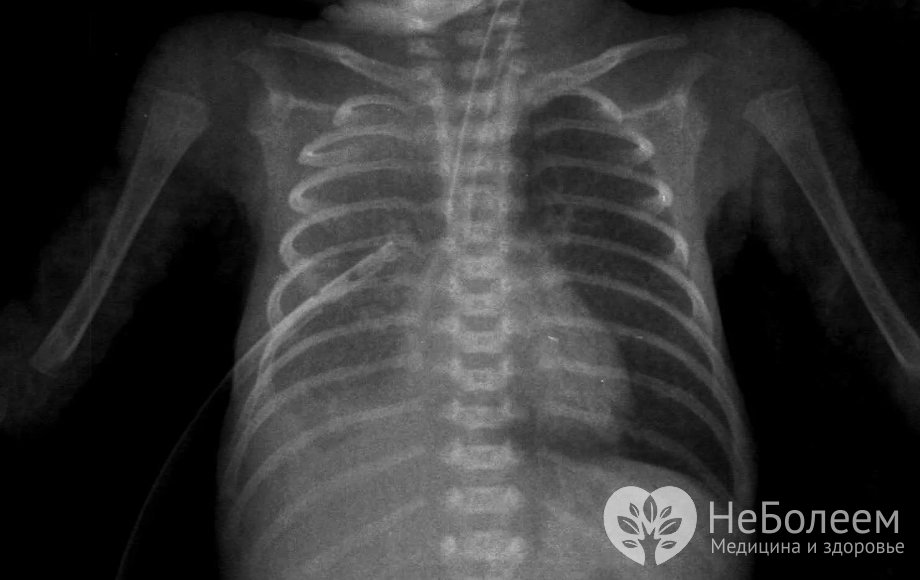

Пневмония у ребенка на рентгеновском снимкеСуществует целый ряд факторов, способствующих развитию пневмонии у детей. К ним относятся:

Диагностика пневмонии у детей осуществляется на основании характерной клинической картины заболевания, данных физикального обследования (выявляются крепитирующие или мелкопузырчатые хрипы, ослабленное дыхание, укорочение перкуторного звука) и результатов лабораторно-инструментального обследования, включающего: